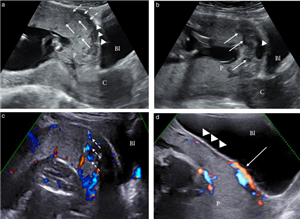

Giá trị của siêu âm trong 3 tháng đầu chẩn đoán nhau xâm lấn bất thường ở thai phụ nguy cơ cao có nhau tiền đạo